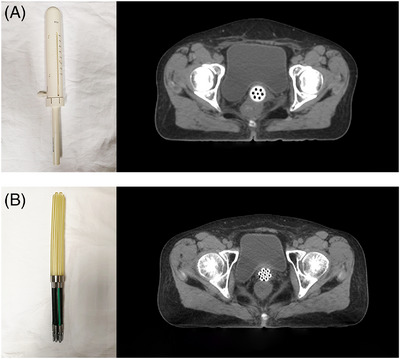

Methods: CT images were obtained postoperatively from 90 patients with gynaecological cancer who underwent vaginal brachytherapy, including 60 and 30 treated with applicators A and X, respectively. A basal model was devised using data from the patients treated with applicator A; next, a DANN model was constructed using these same 60 patients as well as 10 of those treated with applicator X through transfer learning techniques. The remaining 20 patients treated with applicator X comprised the validation set. The model's performance was assessed using objective metrics and manual clinical evaluation.